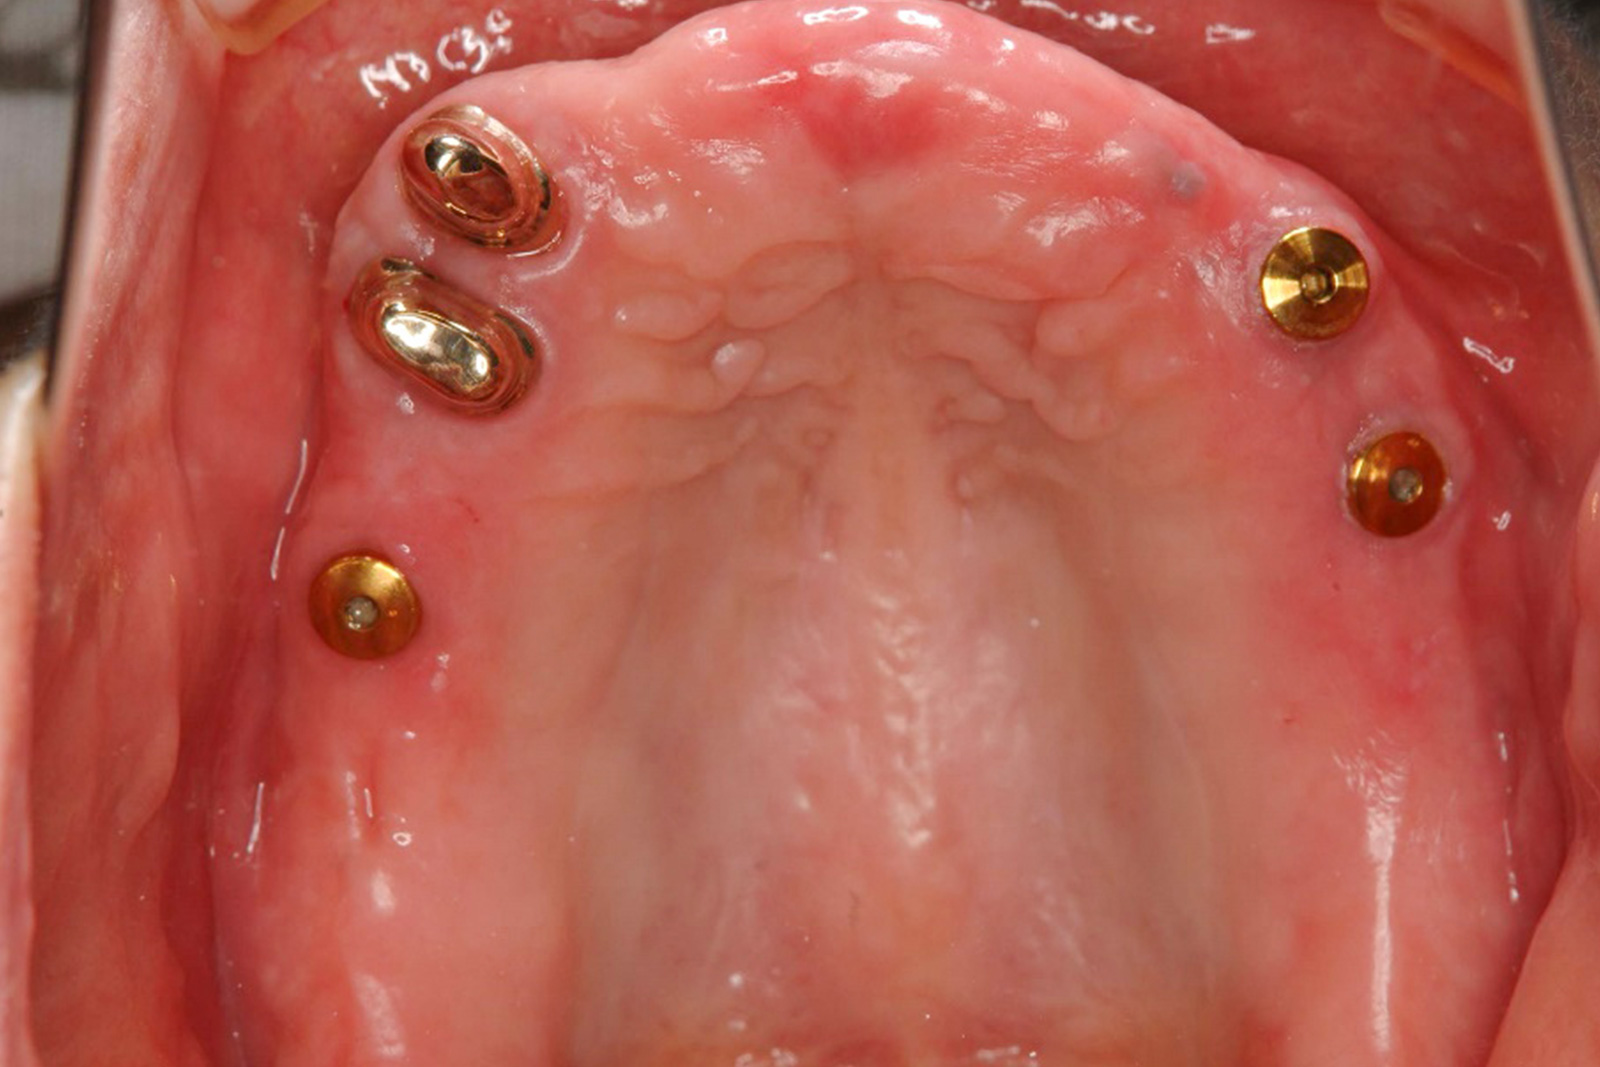

インプラントオーバーデンチャーを使用した症例です。

インプラントオーバーデンチャーは、2~4本のインプラント体を顎の骨に埋め込み、入れ歯を固定させます。

自分で自由に入れ歯を取り外せるため、メンテナンスも簡単です。

インプラントのような大がかりな外科手術も必要ありませんので、体への負担もそれほど大きくありません。

自由診療のため価格は歯科医院によって異なります。当院では88万円~(税込、5年保証)となり、本数によって価格は変動します。